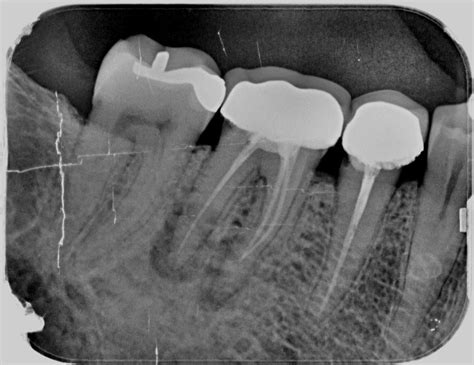

La endodoncia, también conocida como tratamiento de conducto, es un procedimiento que consiste en la eliminación de la pulpa dental inflamada o infectada. Esta pulpa, que está compuesta por nervios y vasos sanguíneos, se encuentra en el interior del diente, específicamente en el conducto radicular. Una endodoncia se realiza con el objetivo de salvar una pieza dental gravemente dañada, debido a una caries profunda, a un traumatismo o a una periodontitis avanzada.

Si estás experimentando dolor dental o sospechas de una infección en la raíz, es fundamental acudir a un especialista cuanto antes. En todo caso, ante cualquier sospecha, debes acudir a tu odontólogo. Será él quien emita un diagnóstico y determine, después de realizar todas las pruebas necesarias -radiografías, test de vitalidad, percusión, etc.-, si el tratamiento endodóntico está indicado.